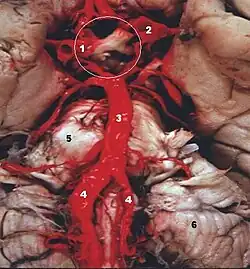

Las dos arterias vertebrales y la arteria basilar proporcionan sangre a la parte posterior del círculo arterial cerebral y se anastomosa con la parte anterior del círculo, irrigado por las arterias carótidas.

Hemodinamia

La dinámica de la sangre arterial en el sistema Vertebral-Basilar, depende de la interacción entre la entrada y la salida del flujo sanguíneo. Las arterias vertebrales determinan el flujo convergente de entrada y las arterias cerebelosa superior y cerebral posterior determinan el flujo divergente de salida de este sistema.[5]